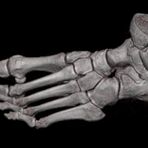

Extremitäten

• bei komplizierten Frakturen z. B. in der Nähe von Gelenken oder im Bereich der Handwurzel und Fußwurzel

Spezielle Software ermöglicht jetzt zum Beispiel:

• verbesserte Bildqualität bei Patienten mit Implantaten (z. Bsp. Hüftendoprothesen)

• besonders hochauflösende, strahlendosissparende Darstellung aller Skelettstrukturen